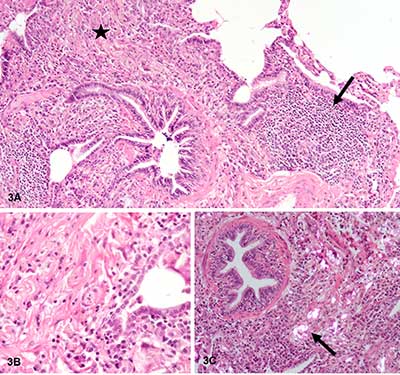

Figure 3

Important non-caseating granulomatous interstitial inflammation, with lymphocytes (black arrow Figure 3A), numerous macrophages and multinuclear giant cells, sitting preferentially in peribronchiolar regions (black star Figure 3A, B). The granulomas contain characteristic needle-shaped birefringent crystalline material in polarized light (black arrow Figure 3C).

Cytology of bronchial alveolar lavage (BAL) showed 16% of neutrophils, 29% of lymphocytes, and 55% of macrophages. There were no eosinophils found. A surgical pulmonary biopsy was performed in order to assess the interstitial pathology. Microscopic examination revealed an important non-caseating granulomatous interstitial inflammation, with lymphocytes (black arrow Figure 3A), numerous macrophages and multinuclear giant cells, sitting preferentially in the peribronchiolar regions (black star Figure 3A, B). These granulomas contain characteristic needle-shaped birefringent crystalline material in polarized light (black arrow Figure 3C). The morphological aspect of these crystals are similar to that of the talc.

Whether inhaled or injected, talc causes non-necroziting granulomatous inflammation that leads to progressive fibrosis. These granulomas are composed of multinucleated giant cells surrounded by a small amount of fibrous tissue. The definitive diagnosis is made by light microscopic examination of lung tissue specimen, obtained by trans-bronchial or open lung biopsy. Talc can be identified as irregular, birefringent needle-shaped crystals inside or outside macrophages under polarized light. The inflammation is organized around bronchioles and small airways in inhaled forms whereas is perivascular in haematogenous spread. The topography around of bronchioles of the granuloma in the biopsies in our case make intravenous form unlikely.